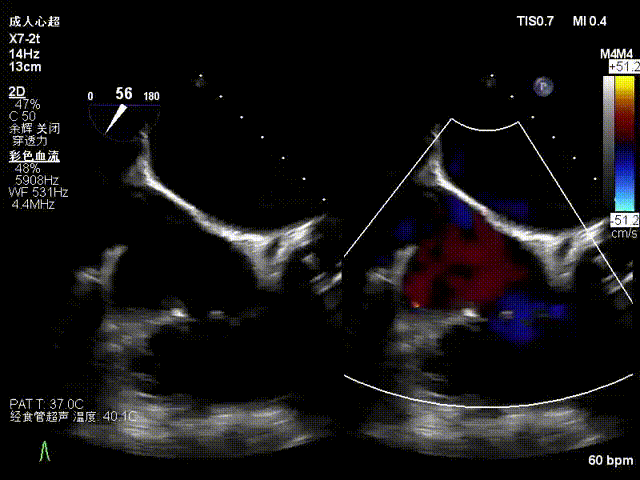

术后超声显示反流基本消失

此次手术全程仅用时一小时十分钟,器械从进入到撤出耗时45分钟,植入一枚夹合器,术后患者即刻超声心动图评估三尖瓣反流由5+下降至1+,手术取得圆满成功。